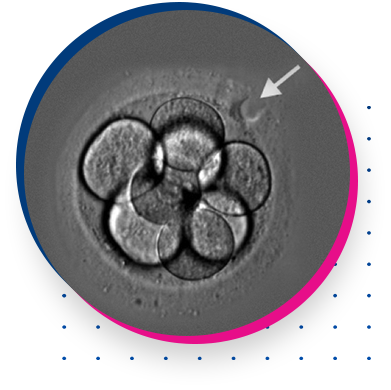

IN VITRO FERTILIZATION (IVF)

EMBRYO FREEZING

ASSISTED HATCHING

Preimplantation Genetic Diagnosis (PGD)

ICSI